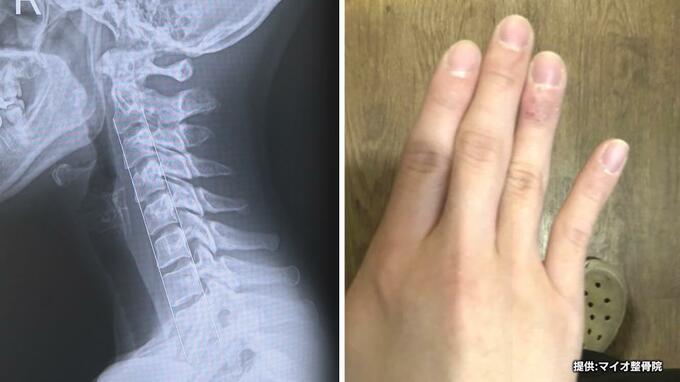

持ち方で変形“スマホ指” 見過ぎで肩こりや頭痛“スマホ首” 整形外科医は「非常に増えている印象」増加する現代病 2024年7月10日(水) 21:28 国内 現代病とも言われる「スマホ指」「スマホ首」。みなさんは大丈夫でしょうか。街の人「小指が広がるみたいな。(広がっている感じは?)指が若干、広がっている」「現代病だなって感じ」 それって、もしかしたら…